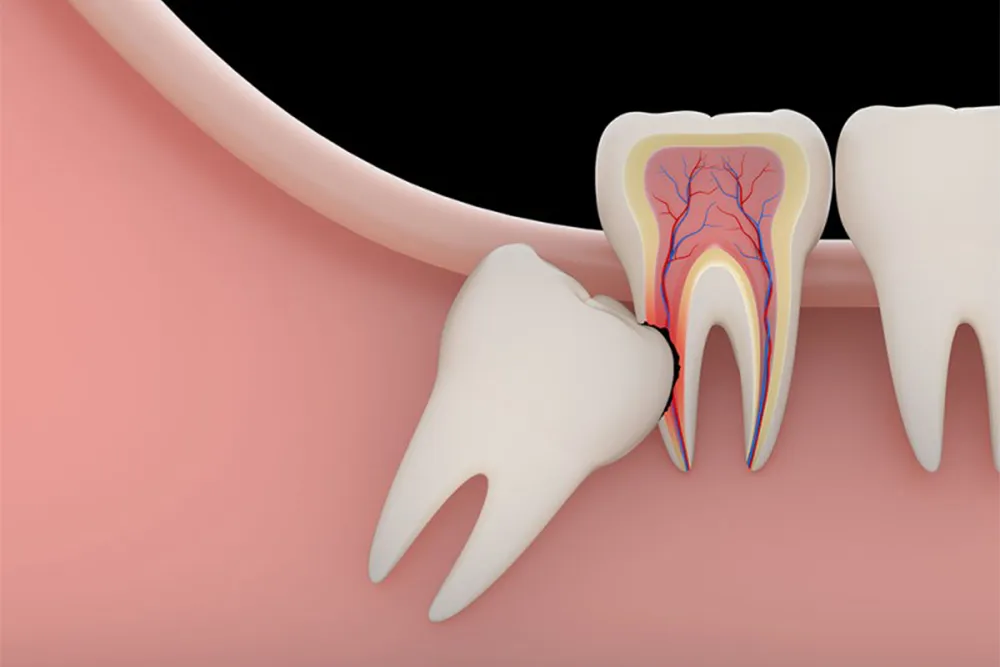

دندان عقل تنها زمانی کشیده می شود که در جهت کج روییده باشد، در دهان قرار نگیرد یا در لثه نهفته باشد. در این حالت دندان عقل باعث التهاب و ناراحتی بیمار می شود و در درازمدت می تواند دندان ها را نامرتب کند. بنابراین برای تعیین زمان مناسب کشیدن دندان عقل باید به ارتودنتیست مراجعه کرد تا معاینه شود. در ادامه اطلاعات بیشتر در مورد زمان مناسب کشیدن دندان عقل ارائه شده است.

در برخی موارد، با توجه به نبود فضای کافی در داخل فک برای رشد و قرارگیری همه دندانها، رشد دندان عقل ممکن است تحت تأثیر محدودیت فضا قرار گیرد. علاوه بر این، دندان عقل در جایی رویش میکند که به ندرت میتوان مستقیماً قابل مشاهده باشد، و گاهی اوقات ممکن است به گونهای رشد کنند که به طور جزئی یا کامل در لثه نهفته شوند. برخی از افراد فکر می کنند که دندان عقل باید کشیده شود زیرا به طور کامل و درست رشد نمی کند. اگرچه این احتمال وجود دارد، اما همیشه اینطور نیست. دندان عقل اغلب فضای کمی برای حرکت دارد، اما جای نگرانی وجود ندارد. رویش دندان عقل برای برخی افراد مشکلی ایجاد نمی کند. اما در صورتی که نیاز به کشیدن دندان عقل بر اساس نظر متخصص ارتودنسی باشد، انتخاب زمان مناسب از اهمیت ویژه ای برخوردار است.

بنابراین نقش دندان عقل در ناهماهنگی دندان ها در بزرگسالی ناچیز است، به طوری که می توان از آن چشم پوشی کرد. با این حال، اگر دندان عقل نابجا باشد و به طور جزئی یا کامل نهفته باشد، می تواند مشکلاتی مانند التهاب لثه ایجاد کند. در این صورت بیمار چه قصد انجام ارتودنسی را داشته باشد یا خیر، باید به دندانپزشک مراجعه کند و دندان عقل خود را بکشد.